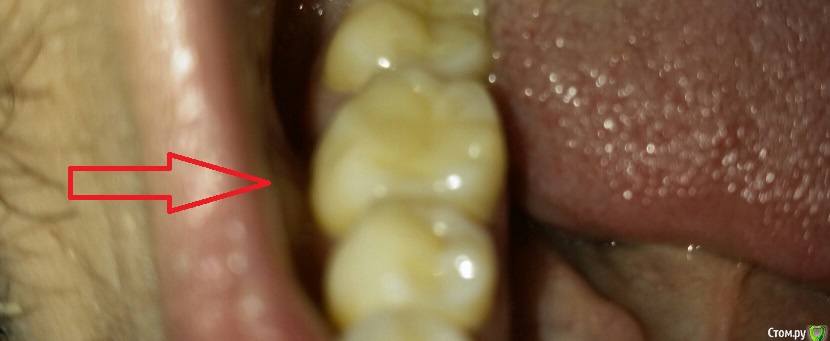

aleksei_sataev Опубликовано 22 июня, 2015 Автор Поделиться Опубликовано 22 июня, 2015 (изменено) Если боли при возникает когда твердое попадает на пломбу, то пломбу нужно переставить.Вы у своего врача были? Да когда попадает твердое да и не совсем твердое. А вчера когда пил холодный коктейль, совсем немного отдало в зуб, болью это назвать тяжело. Да у врача был, он вставлял копирку и проверял прикус. Вроде всё хорошо с его слов, а с моих есть пищу не приятно... Изменено 22 июня, 2015 пользователем aleksei_sataev Ссылка на комментарий